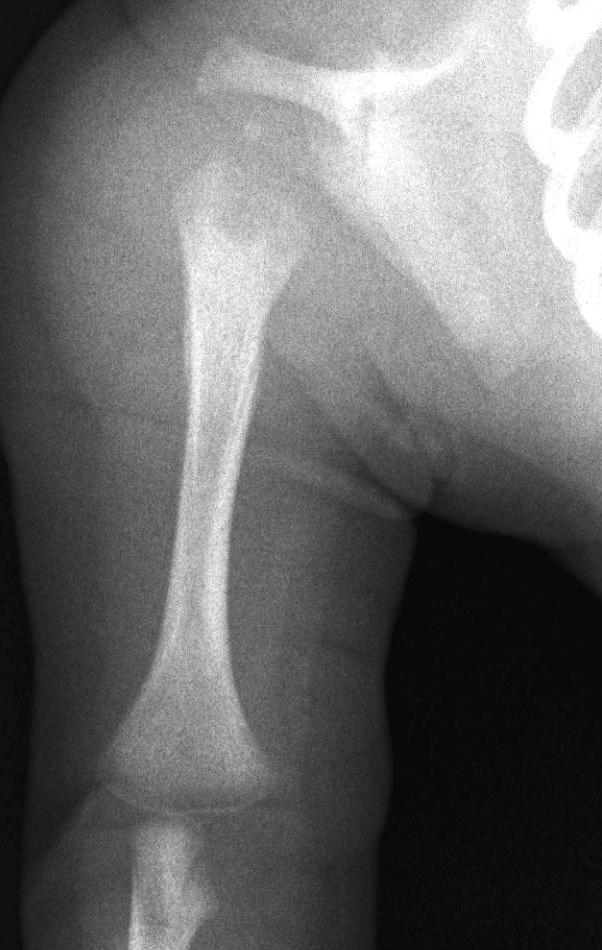

Wilms tumor. It is the most common kidney tumor in childhood that appears between 2-5 years of age. It is usually only noted when the tumor is palpable as an abdominal mass. Hematuria, hypertension, vomiting and abdominal pain are also part of the clinical picture. US examination is a basic method in both the diagnostics and the follow-up of the tumor. The tumor is normally seen as a homogenous or an inhomogeneous mass, dislocating the pyelon and the surrounding retroperitoneal blood vessels. It is important to rule out any lesion in the other kidney. MRI examination: gives a picture of the entire abdomen, kidneys included. Nodal metastases, tumor thrombus are well depictable. CT-examination: is to be chosen if MRI is not available. The tumor shows an inhomogeneous contrast enhancement and pulmonary metastases (invisible to x-ray examination) are also depictable.

Image

27. A solid, echogenic mass arising from the right kidney. Wilms tumor. Abdominal US.

28. MRI examination axial, T2weighted sequence. A solid mass arising from the right kidney and filling out the right side of the abdomen, with peripheral follicular cystic components. Wilms tumor. (with the courtesy of Dr. Gábor Rudas)